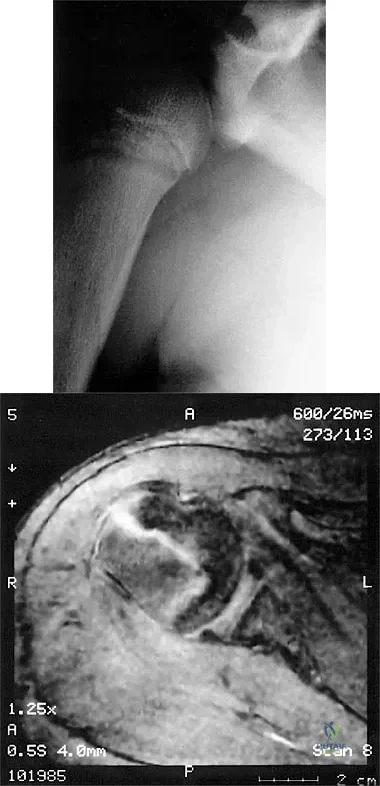

Question 33

A 37-year-old electrician is diagnosed with a frozen shoulder after sustaining an electrical injury at work 2 weeks ago. Examination reveals that he cannot actively or passively externally rotate or abduct the arm. The glenohumeral joint and scapula move in a 1:1 ratio. Radiographs are shown in Figures 15a and 15b. The best course of action should be

Explanation